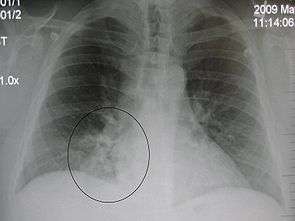

| A chest X-ray showing a very prominent wedge-shape bacterial pneumonia in the right lung. | |

Right upper lobe pneumonia as marked by the circle.- Left upper lobe pneumonia with a small pleural effusion.